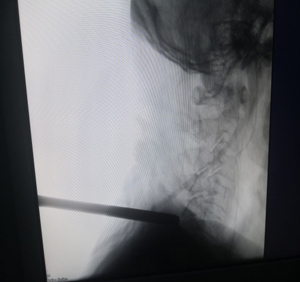

术中精准定位

3.安全性高:全程X线辅助定位+可视化屏幕,手术采用局部麻醉,可及时与患者沟通,降低高龄患者麻醉风险及神经损伤几率。